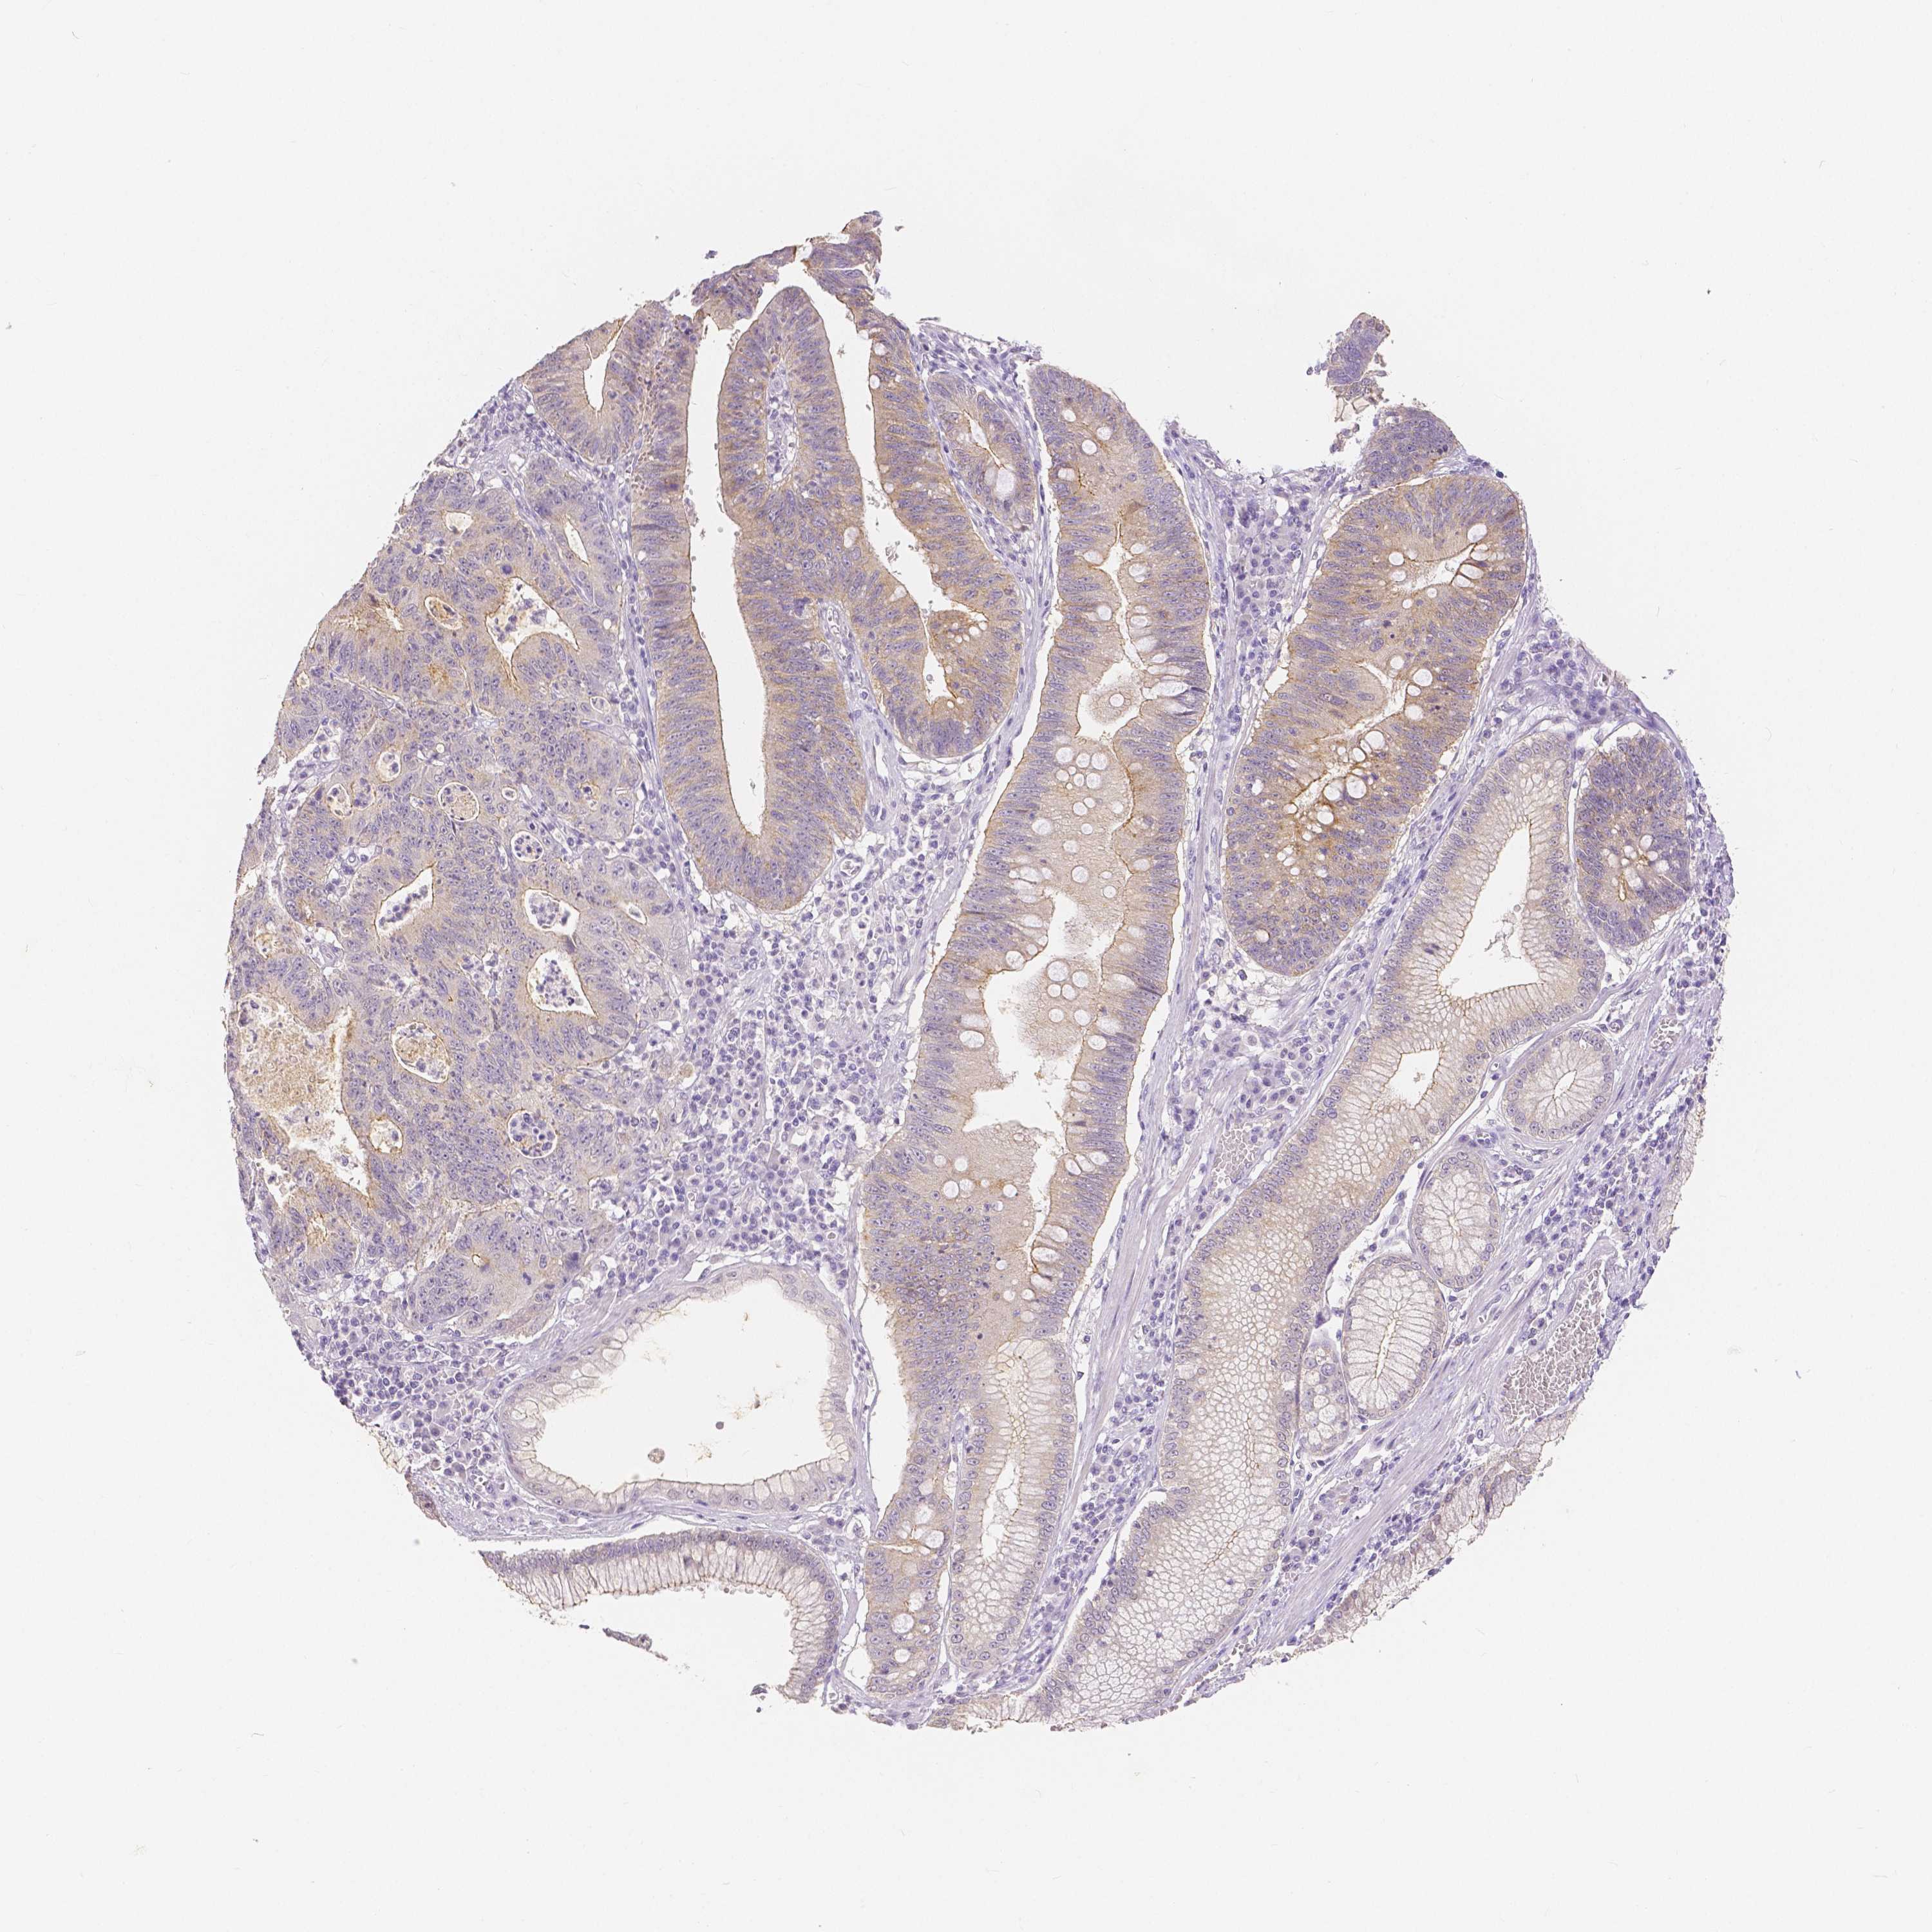

STOMACH CANCER - Protein expressioni

A mouse-over function shows sample information and annotation data. Click on an image to view it in a full screen mode. Samples can be filtered based on level of antibody staining by selecting one or several of the following categories: high, medium, low and not detected. The assay and annotation is described here.

Note that samples used for immunohistochemistry by the Human Protein Atlas do not correspond to samples in the TCGA dataset.

Antibody stainingi

Antibody staining in the annotated cell types in the current human tissue is reported as not detected, low, medium, or high, based on conventional immunohistochemistry profiling in selected tissues. This score is based on the combination of the staining intensity and fraction of stained cells.

Each image is clickable and will lead to virtual microscopy that enables deeper exploration of all samples and also displays staining intensity scores, fraction scores and subcellular localization as well as patient and tissue information for each sample.

HPA005933

CAB013075

CAB068212

CAB068213

CAB068214

Adenocarcinoma, NOS

Adenocarcinoma, High grade